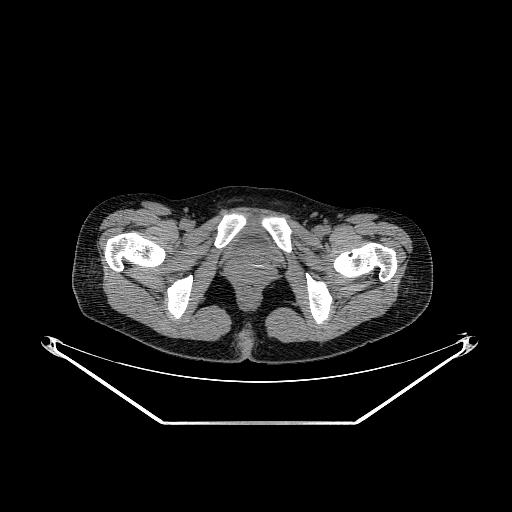

以下是引用ct诊断高手在2009-5-29 13:50:00的发言:[br]考虑左侧中央型肺癌,阻塞性肺炎伴肺不张。纵隔淋巴结转移。慢支 肺间质纤维化肺气肿。左侧胸腔积液。左侧肋骨转移?

以下是引用hhcckk在2009-5-29 14:58:00的发言:[br]左上周围型肺癌,左肺门、纵隔淋巴结转移,左侧胸腔积液,左侧肋骨转移[br]